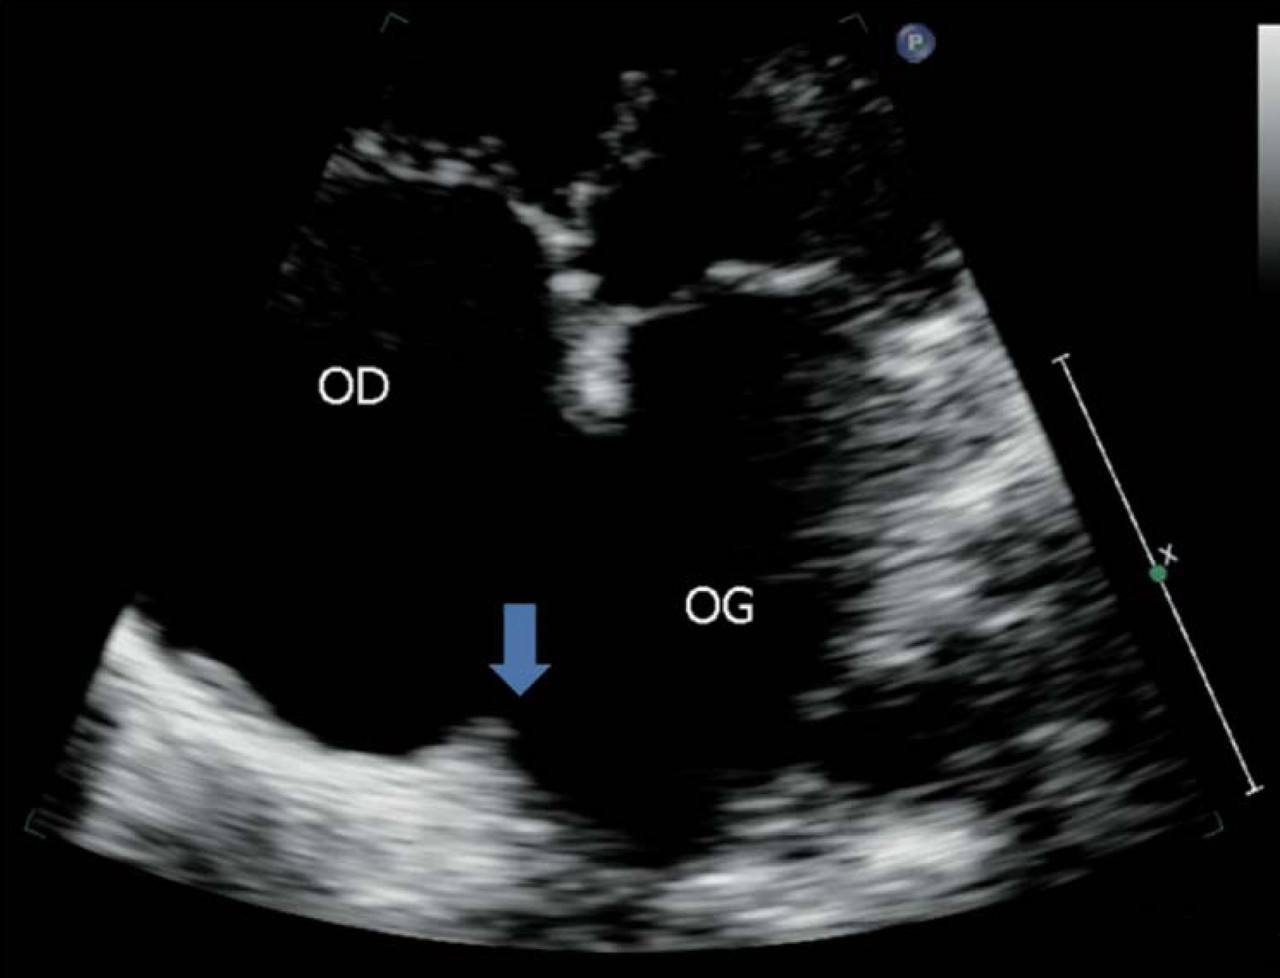

Il s’agit d’une cardiopathie congénitale. L’échocardiographie transthoracique (vue 4 cavités) montre ici une large communication interauriculaire avec peu de berge postérieure (flèche), rendant cette communication interauriculaire peu propice à la fermeture percutanée. Mais seule l’échocardiographie transœsphagienne, voire la tentative de fermeture percathétérisme, permettra de confirmer sa non-faisabilité. Si la fermeture des communications interauriculaires de type sinus venosus et ostium primum est toujours chirurgicale, les communications ostium secundum sont majoritairement fermées par cathétérisme interventionnel. Alors qu’initialement, seules les communications d’un diamètre maximal de 20 mm et centrales étaient fermées par cathétérisme, il est possible aujourd’hui de fermer des communications ayant jusqu’à 38 mm de diamètre, voire un peu plus, ce qui représente environ 80 à 90 % d’entre elles. Les limites sont la dimension totale du septum et l’existence de berges. Les larges communications ayant peu ou pas de berge postéro- inférieure sont peu propices à la fermeture percutanée comme ici. Pour en savoir plus : - Iserin L. Quelles cardiopathies congénitales posent des problèmes à l'âge adulte ? Rev Prat 2013;63(3):363-8. - Thambo JB. Rôle du médecin généraliste dans le suivi des cardiopathies congénitales à l'âge adulte. Rev Prat 2013;63(3):369-74. - Schouvey S, Assaidi A, Fraisse A. Communication interauriculaire à l'âge adulte. Rev Prat 2013;63(3):375-6. - Ladouceur M, Cohen S, Bidet M, Legendre A, Iserin L. Contraception et cardiopathies congénitales. Rev Prat 2013;63(3):377-9.